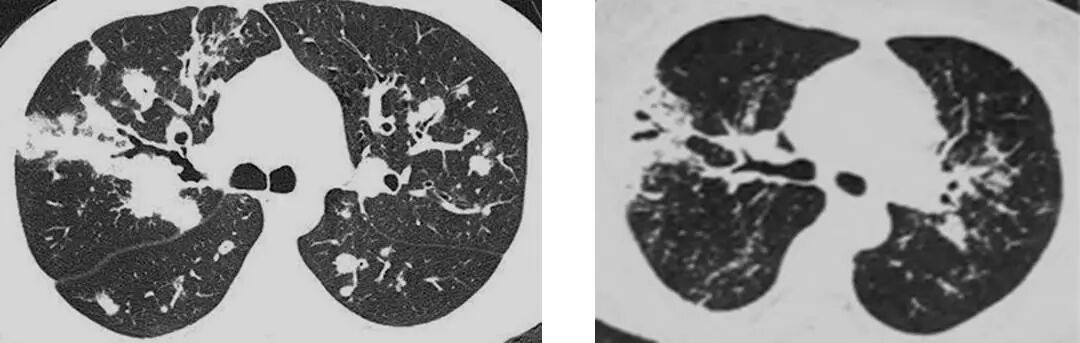

▶结节肿块型

▶肺炎肺泡型

▶支气管血管淋巴管型(间质型)

▶粟粒型

▶混合型

MALT 的支气管扩张并无支气管管壁的破坏。由于淋巴瘤组织浸润导致肺泡塌陷,支气管周围实质破坏造成的,这类支气管扩张在肿瘤治疗后有时可消失。

肺粘膜相关淋巴瘤

结节、肿块,边缘模糊

充气支气管粗大、扭曲